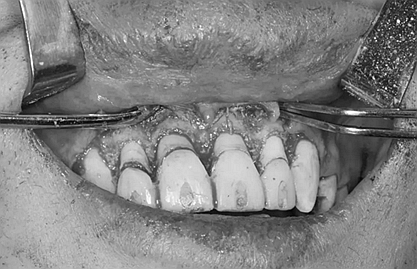

下面是醫(yī)生眼中和ct下的我們

一身病痛啊

牙結石、牙齦炎癥、牙體殘缺、慢性牙髓炎、蛀牙......

治療是從5月份開始的,醫(yī)生給我的主人驗了血,做手術前的準備,還給我們都用超聲波好好的都洗了個澡,把之前依附在我們身上的牙結石都沖了個干凈(齦上潔治術)。治療先從我和其他3個兄弟開始。在麻藥的作用下,我們兄弟4個都被打開了身體,去除了已經被蛀牙破壞的牙體,做了根管治療。